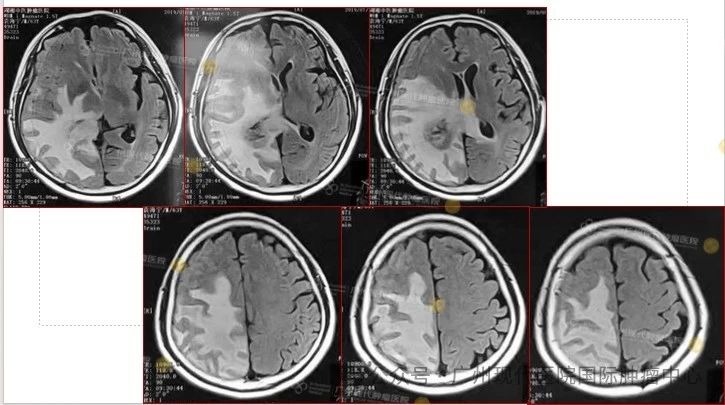

患者:63歲,男性

2013-11,體檢發(fā)現(xiàn)肺部腫瘤,

2015-11,頭顱MR檢查提示顱內(nèi)轉(zhuǎn)移

2018-11,顱內(nèi)腫瘤進(jìn)展,無(wú)法接受后續(xù)治療

2019-3,接受腦瘤粒子植入術(shù)

2019-7,顱內(nèi)腫瘤基本消失,正常生活至今

2019年7月,顱內(nèi)腫瘤已基本消失